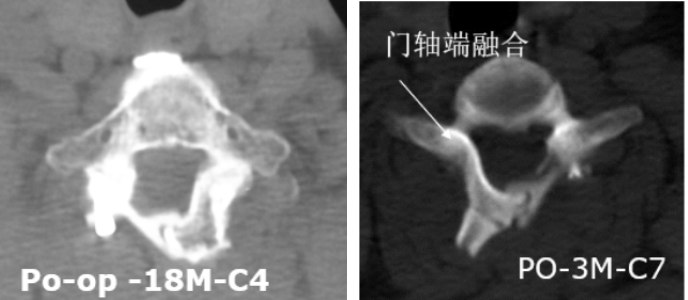

3.有效防止术后再关门,为脊髓提供强力保护

4.可融合,远期稳定性好